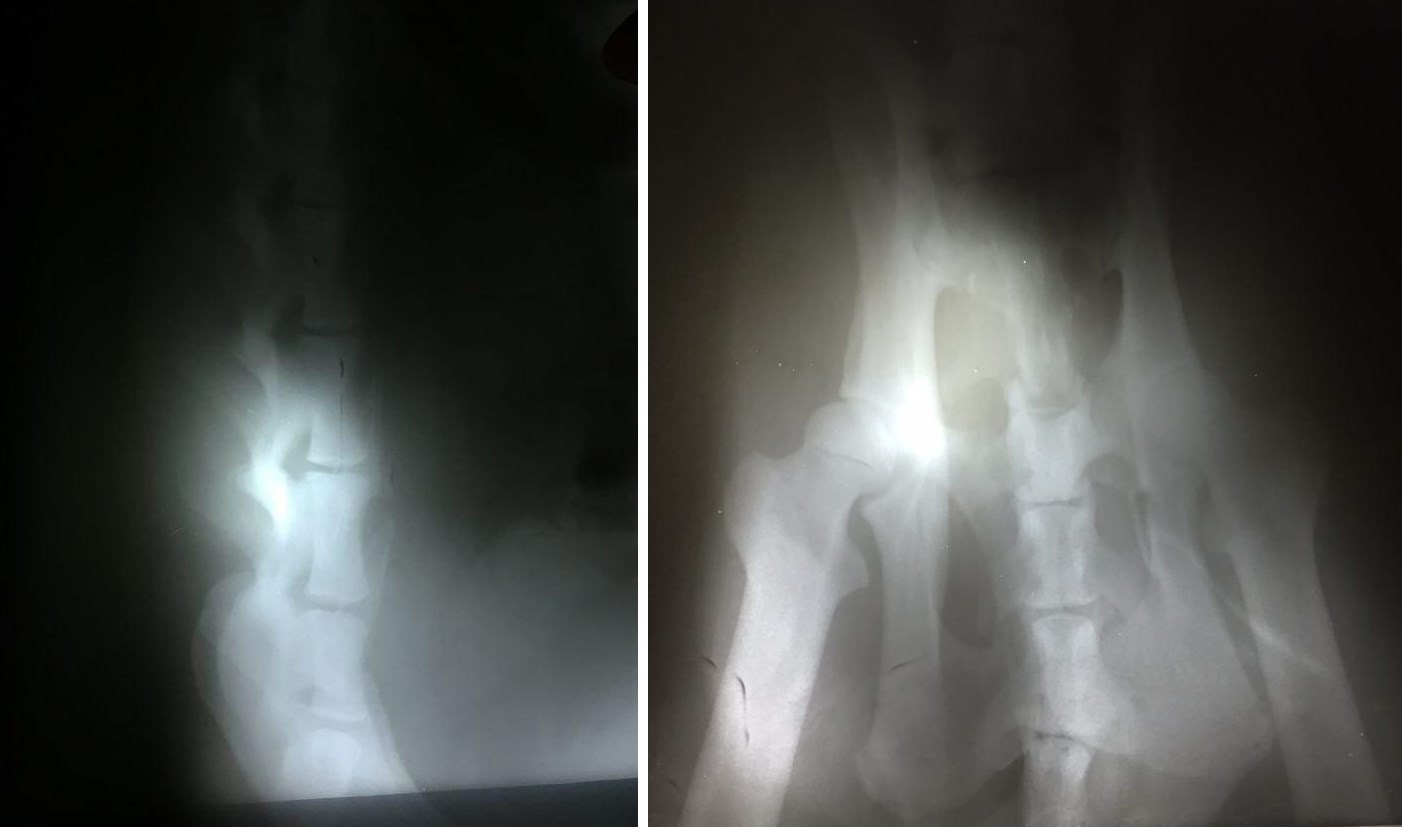

مسلم آهنگری فرمانده یگان حفاظت محیط زیست استان مازندران با اعلام این خبر به خبرنگار اجتماعی خبرگزاری تسنیم میگوید: ظاهراً این پلنگ نر که پس از زندهگیری، توسط دامپزشک مورد معاینه و رادیوگرافی قرار گرفت دچار شکستگی نشده است. این حیوان ساعتی پیش به جایگاهی در پناهگاه حیات وحش سمسکنده منتقل شد تا پس از به هوش آمدن و مشاهده واکنشها درباره امکان رهاسازی آن تصمیم گرفته شود.